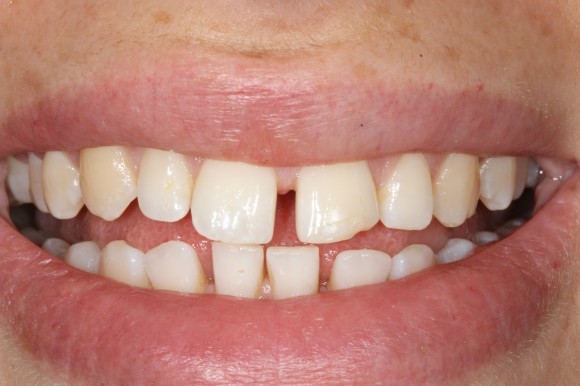

Causes Of Diastema Between The Teeth

When you have extra space between two or more of your teeth, your doctor calls this spacing issues or gap teeth. Gappy teeth are quite common, but sometimes they can become a bit of a bother. Maybe you don’t like the look of them or find that food gets trapped, causing issues with your gums.

Gap teeth can create pockets between your teeth and gums where food can get stuck. It can make your gums tender and sore and even lead to gum disease. Fortunately, that gap doesn’t have to be permanent.

Causes Of Gaps Between The Teeth:

Gapped teeth, which are also called diastema, cause distinct gaps between the teeth. Diastema is a term used most often for the gap between the front two upper teeth, the most common gap in the mouth. 50-60% of children under the age of 5 have this gap, and it will usually close on its own by the age of 8 or 9. If the gap hasn’t closed even after the adult canine and incisor teeth have come in, it may not close on its own at all.

Aside from genetics, there are a few other reasons why gaps in the teeth may develop. For example, if there is a size mismatch between your child’s jaw and teeth size, there may be extra room in the jaw for the teeth to space apart. Additionally, childhood habits like pacifier use or thumb-sucking can also result in gaps between the two front teeth.

Another cause of gaps in the teeth is frenum issues. The maxillary labial frenum is a strip of tissue that connects the underside of the upper lip to the gum tissue between the two front teeth. If this strip of tissue is too thick, it can prevent the two front teeth from closing together.

Closing Dental Gaps:

Gaps in the teeth can be closed in a number of ways. The most common fix for gapped teeth is through the use of orthodontic braces. But other cosmetic procedures can be used to close the gap, including dental veneers, a dental bridge or implant or even partial dentures. The treatment depends on the location of the gap and why it’s occurring.

Gaps in the teeth can cause problems with speech and self-esteem. Luckily, there are a number of ways to achieve the smile you’ve always wanted and would be proud to show off!